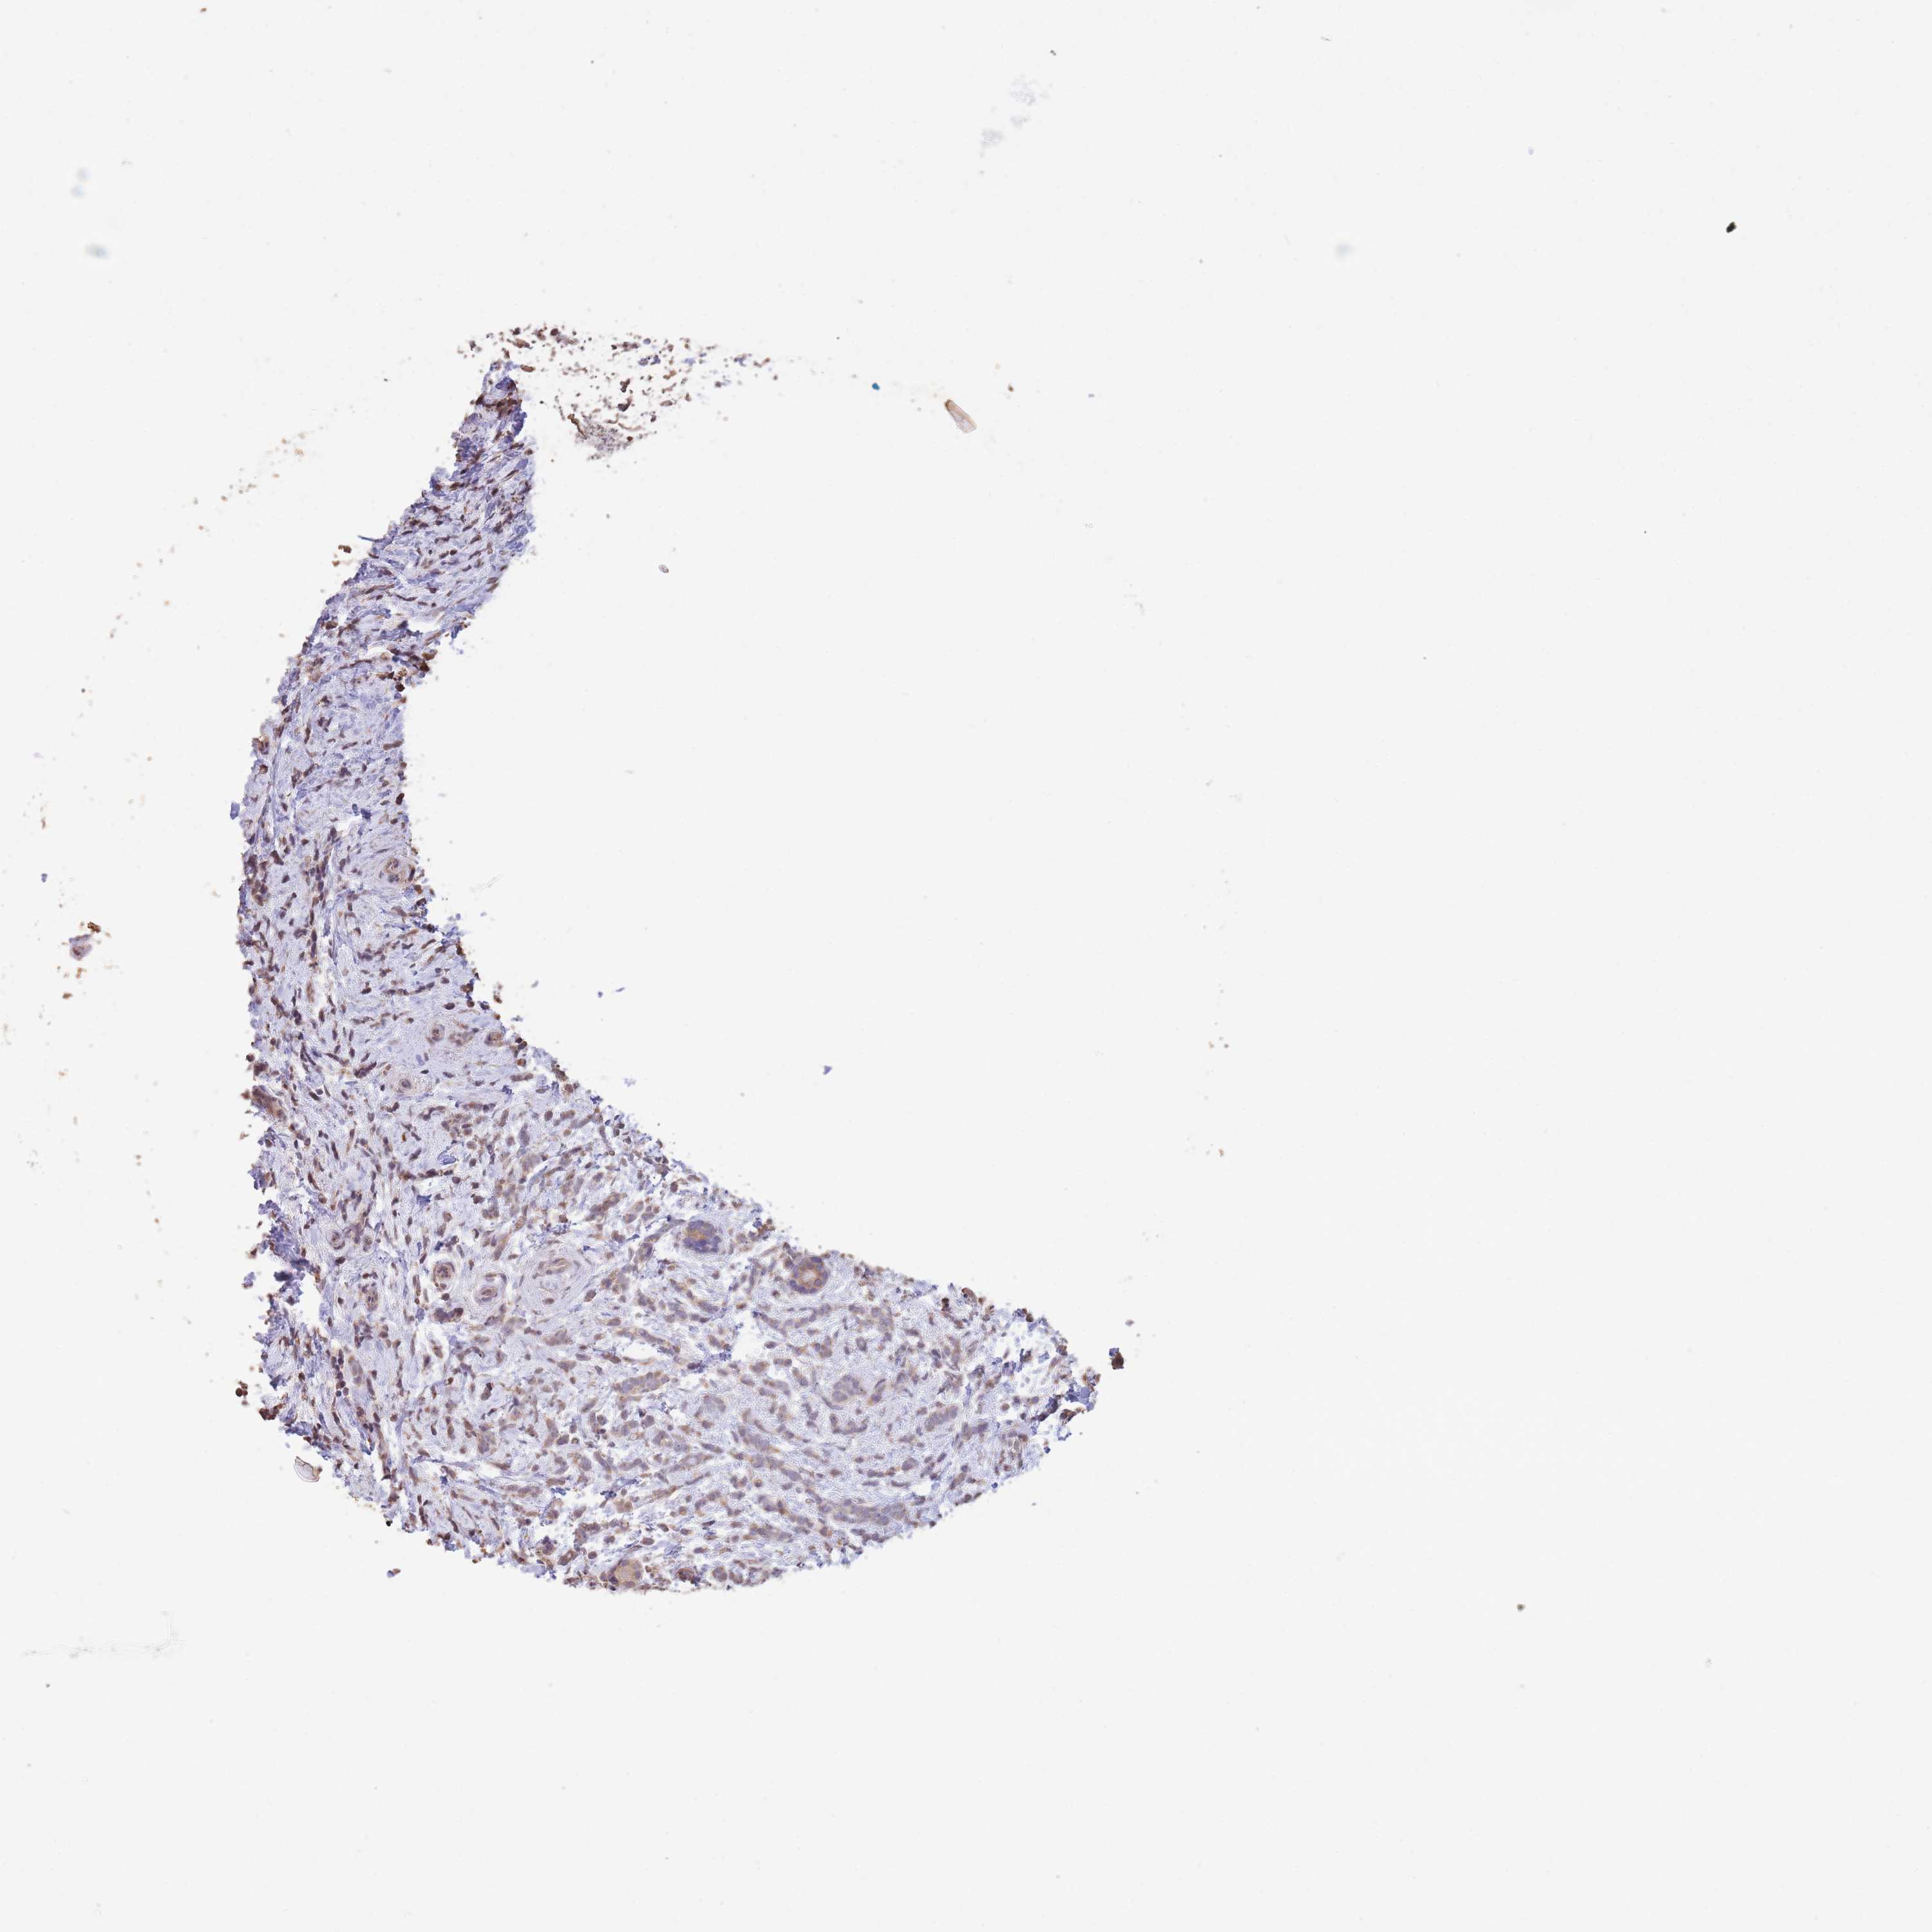

CANCER BREAST CANCER Show tissue menu

BRCA TCGA BRCA VALIDATION PROTEIN EXPRESSION